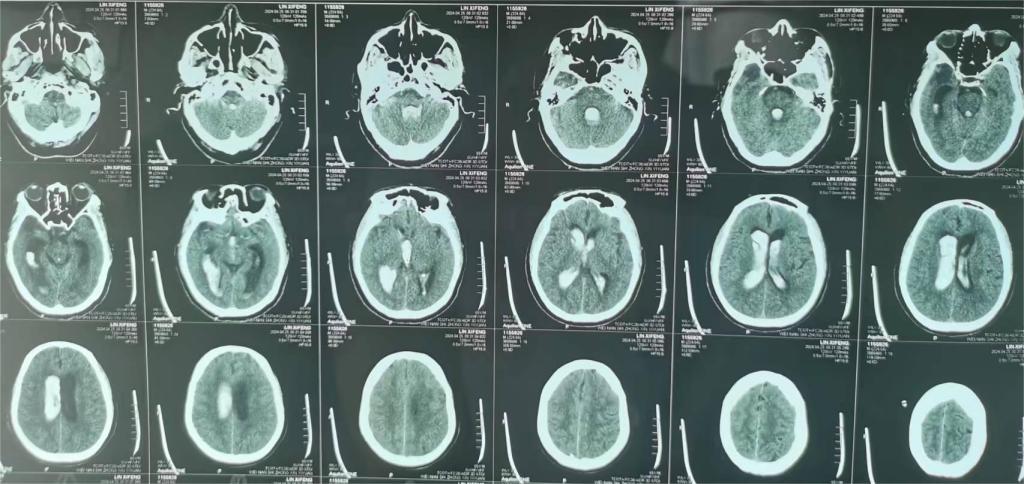

患者男性,65岁,意识不清3小时转入医院,颅脑CT提示脑室出血并脑疝。入院时患者血压175/105mmHg,深度昏迷,对光反射消失,四肢刺痛无反应,肌张力减低,双侧巴氏征阳性。

术后2周

术后一个月